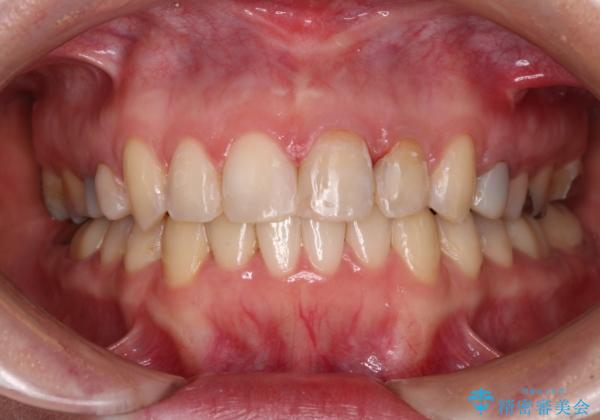

- 前歯のデコボコと奥歯の虫歯を気にして来院された患者様です。

主に下顎歯列全体の後方移動とIPR(歯と歯の間を削る)によってデコボコが解消するように設計し、インビザラインにより治療を行うこととしました。

矯正治療後半に下顎左右奥歯をセラミッククラウンにて補綴し、その後インビザラインによる歯列の仕上げを行うこととしました。

下顎前歯の叢生が速やかに改善されたため、1年3か月で治療を終えることができました。

下顎前歯は後戻りを起こしやすいため、舌側を細いワイヤーで固定することで後戻り対策を行っています。